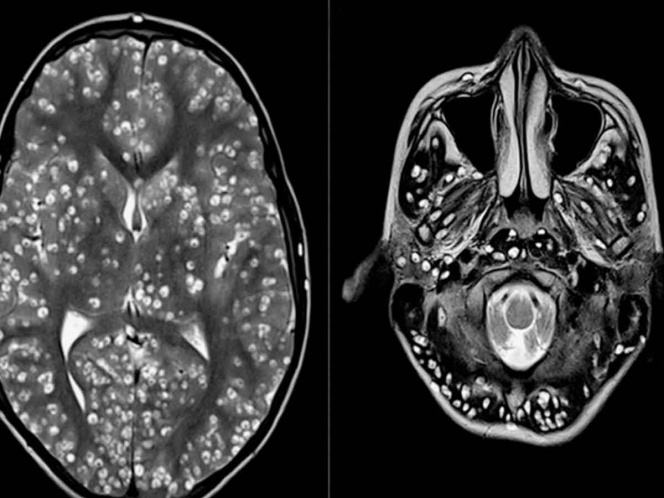

Tras practicarle una resonancia magnética y exámenes de ultrasonido, los especialistas encontraron que la corteza cerebral y el tronco encefálico del paciente estaban llenos de larvas.

El muchacho padecía neurocisticercosis, una enfermedad parasitaria originada cuando una persona ingiere huevos microscópicos de una tenia porcina y que afecta al tejido muscular. De ahí los parásitos se propagan al cerebro. Los personas infectadas pueden pasar mucho tiempo sin presentar síntomas.